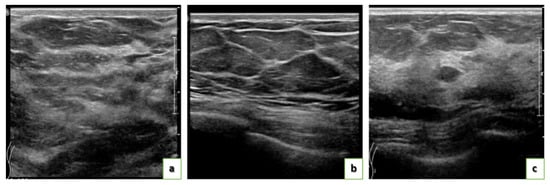

US Images

| Modality | Mammogram, Ultrasound (US) |